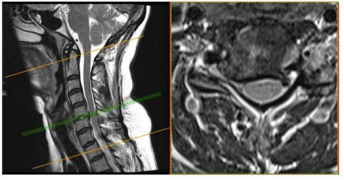

Uma paciente de 47 anos de idade apresenta quadro de

cervicobraquialgia direita há cerca de três meses, associada a

parestesia no membro superior direito, que se estende até

mão, principalmente nos dedos indicador e polegar. Ao

exame fisico, nota-se leve redução do reflexo

braquioestilorradial. O teste de Spurling foi positivo à direita.

Observou-se ausência de paresias.

No citado caso clínico, foi solicitada uma ressonância magnética cervical, conforme representado nas figuras. Esse exame evidencia uma